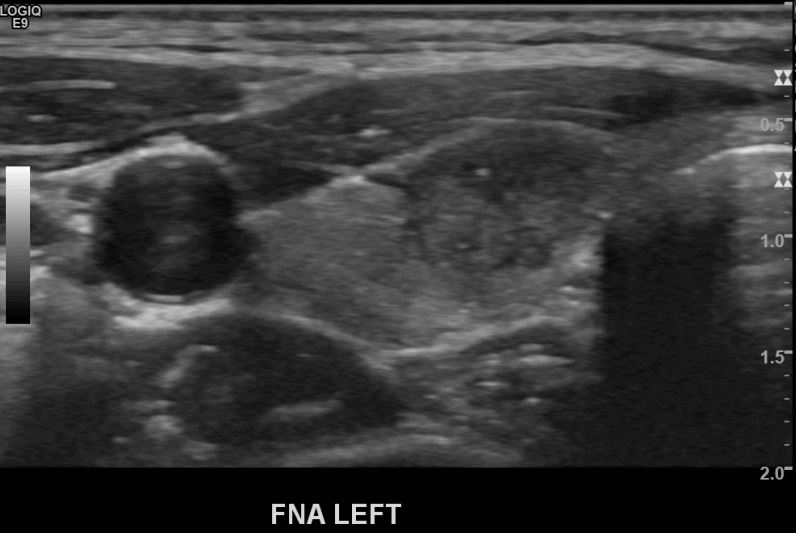

상기환자  20대후반 여성분으로 의심스러운 좌엽혹 세포검사진행후 갑상선암으로 진단되었습니다